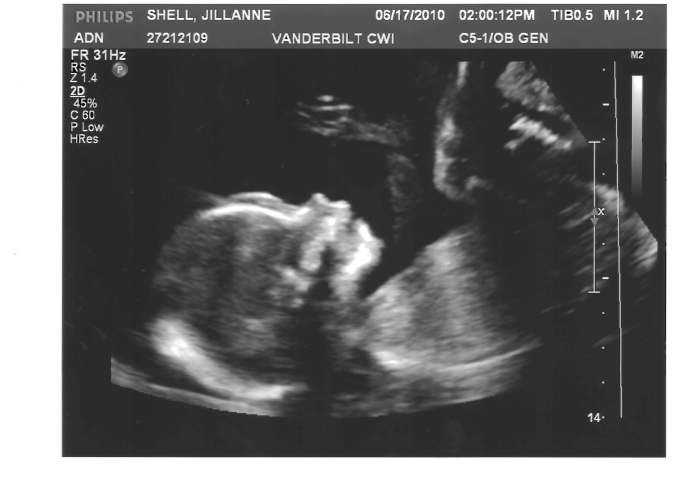

Most importantly, Baby Jack is healthy, thank God!